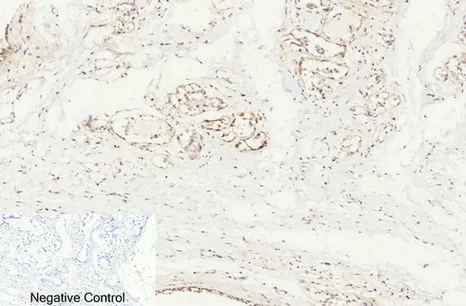

E-Selectin Rabbit Polyclonal Antibody

Cat: APRab10626